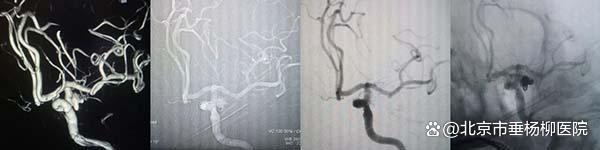

病例1:“密网支架”辅助弹簧圈栓塞血泡样动脉瘤

70岁的孟先生突发蛛网膜下腔出血,脑血管造影显示左侧颈内动脉眼动脉段血泡样动脉瘤,团队采用“血流导向装置”(密网支架)置入,通过改变血流方向,并填塞一枚弹簧圈,降低动脉瘤复发率。